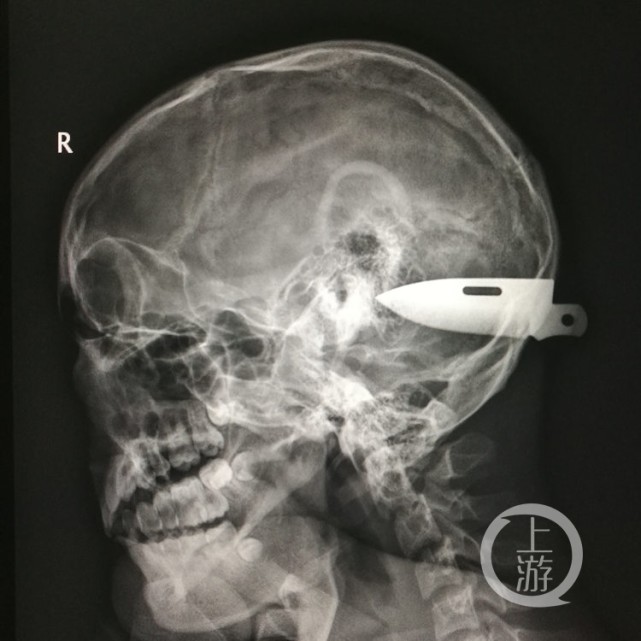

CT和取出的刀片。医院供图

飞刀长达8厘米 横贯小脑“脑花”

刀片取出后,测量长达8厘米。这8厘米的刀片,穿过后脑勺的颅骨,横贯小脑的“脑花”。刀尖的破口离脑部乙状窦只有2毫米,刀刃破口离横窦5毫米,“这两个窦是颅内最重要的静脉,几乎颅内所有的血液都通过它们回流到心脏。”一旦它们被刀刺断,就会导致不可控制的大出血,后果将不堪设想。